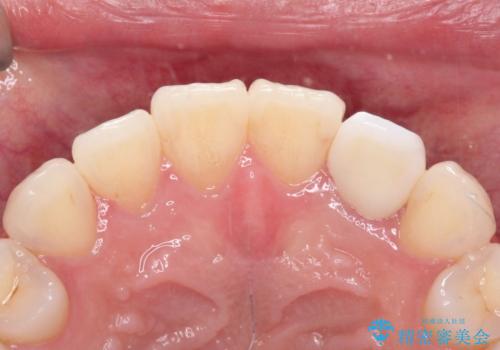

前歯の変色 オールセラミッククラウン

根管治療後、オールセラミッククラウン(エクセレント)にて治療を行なっています。

オールセラミッククラウン(エクセレント)は、技工士さんが立会う事で色調や形態の相談を行うことができ、満足度の高い治療を行うことができます。